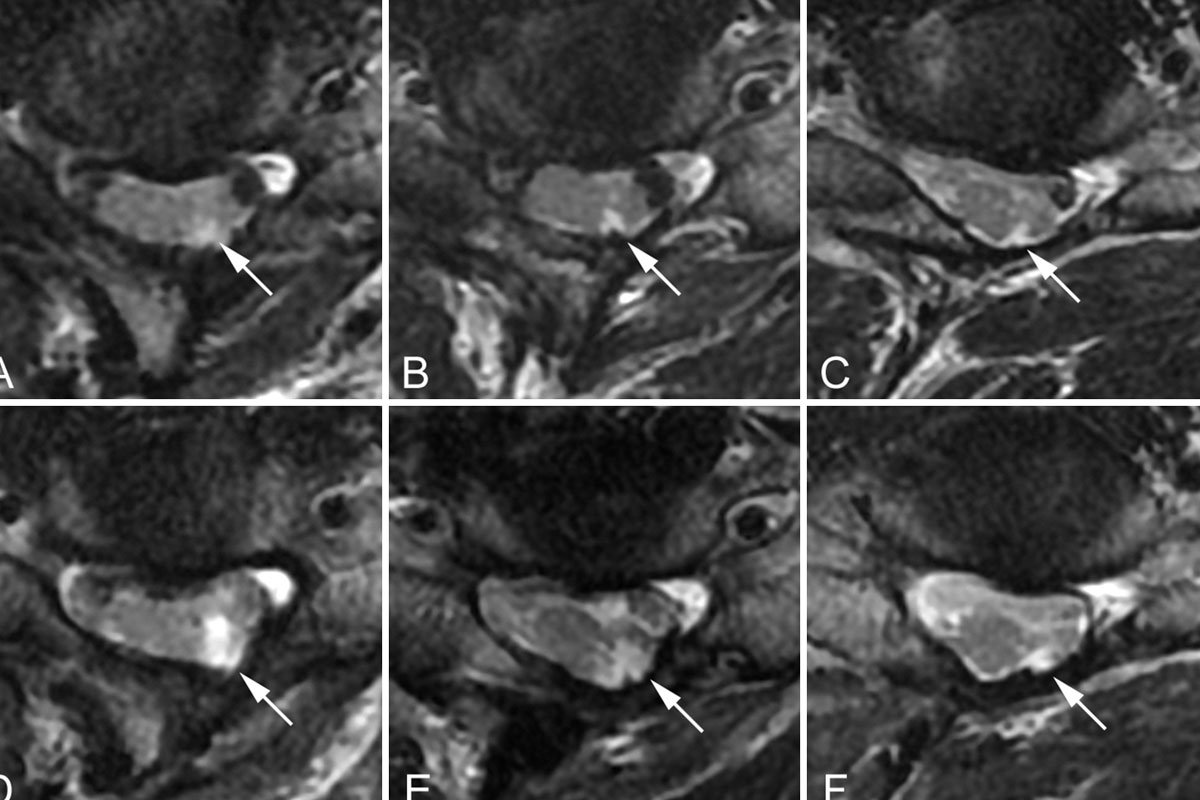

Lumbar Disc Problem

Degenerative thoracolumbar disorders are becoming increasingly prevalent as patients have longer, healthier, and more active lives. While much of the treatment is non-surgical, there are certain conditions that require surgery. Some degenerative diseases can be easily treated with small, minimally invasive procedures, but others require large, reconstructive operations.

Dr. Sujit Kumar Vidiyala, a professional spine surgeon in Hyderabad, Secunderabad, India, has considerable experience treating the entire spectrum of degenerative disorders, as well as in-depth knowledge of the success rates of each procedure. Mini open and minimally invasive transthoracic disc surgery is performed here.

Conditions that can be treated

- Disc herniations / Prolapse

- Lumbar Stenosis

- Degenerative adult scoliosis

- Kyphosis

- Facet joint arthroplasty

- SI joint degeneration

- Spondylolisthesis